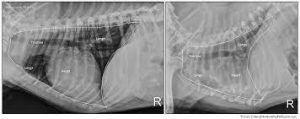

Bác sĩ thú y sẽ kiểm tra các triệu chứng, sử dụng ống nghe để nghe phổi và có thể chụp X-quang để kiểm tra tình trạng phổi. Đôi khi, họ sẽ lấy mẫu dịch phổi hoặc nước mũi để xác định loại vi khuẩn gây viêm phổi. Xét nghiệm máu cũng có thể được thực hiện để phát hiện tình trạng viêm phổi ở chó.

Hãy đảm bảo bạn tuân thủ đúng hướng dẫn và đơn thuốc do bác sĩ thú y cung cấp để giảm nguy cơ tái phát bệnh. Thông thường, quá trình hồi phục mất ít nhất 3 đến 5 tuần và chó của bạn có thể cần dùng kháng sinh trong ít nhất 4 tuần. Bác sĩ thú y sẽ thực hiện chụp X-quang ngực sau khi chó đã dùng thuốc kháng sinh trong 2 tuần để kiểm tra tiến triển và xác định thời gian cần cho việc hồi phục.